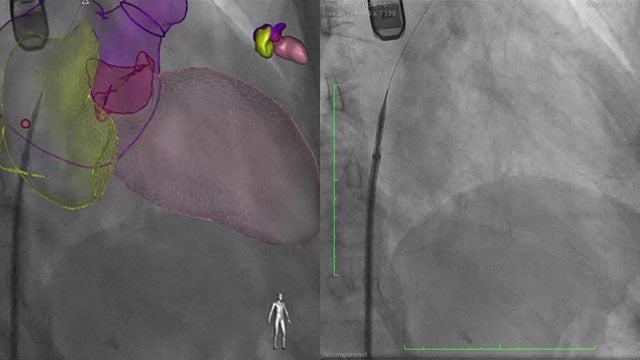

A challenging valve-in-valve scenario in a patient with prior aortic coarctation repair

A 79-year-old with a degenerated aortic bioprosthesis after complex coarctation surgery challenges conventional strategies. Which access route would you choose?